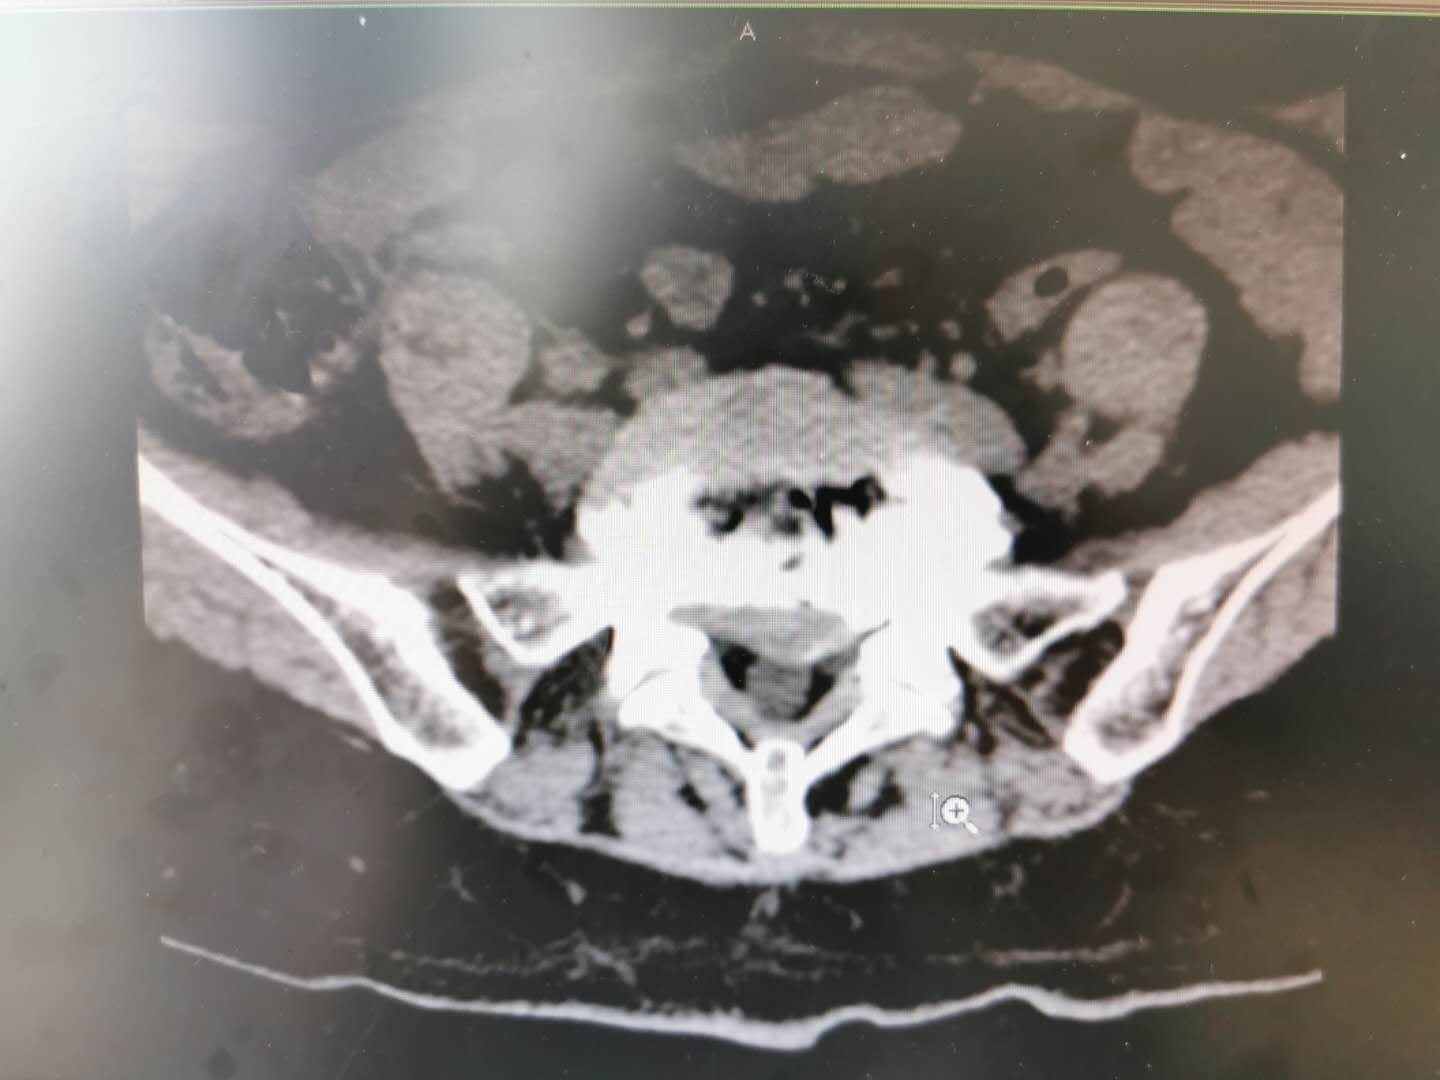

74岁,老年女性,反复腰痛十余年。近半年腰痛症状突然加重,同时伴有明显的左下肢放射痛,痛感十分剧烈,行走时必须弯着腰,卧床休息疼痛也不能缓解,夜不能寐。左侧直腿抬高试验10度。在外院尝试的口服药物,针灸,理疗,按摩均无效。在我院查X线提示腰椎退行性侧弯。CT提示腰4/5椎间盘突出。腰5/骶1椎间盘脱出。